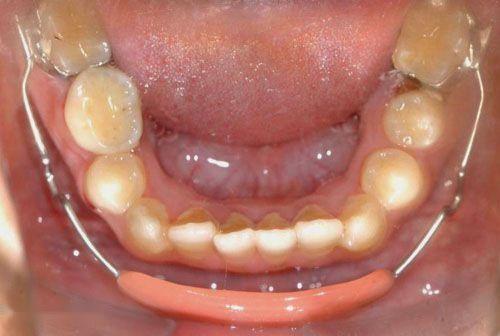

2. 后牙反合

后牙反合表现为下后牙咬在上颌后牙的外侧、上牙弓狭窄。单侧后牙反合患者会出现不同程度的颜面不对称,当上牙弓进一步狭窄时,会形成双侧后牙反合,影响其咀嚼。

矫治方法:后牙反合的患儿往往因为有龋齿而形成偏侧咀嚼的习惯,应及时治疗后牙区龋齿,纠正其偏侧咀嚼的习惯。乳牙列和混合牙列期的主要治疗方法主要通过调合以及扩展上牙弓宽度。常用的矫治器为Haas扩弓器和Hyrax扩弓器。

Haas扩弓器

Hyrax扩弓器